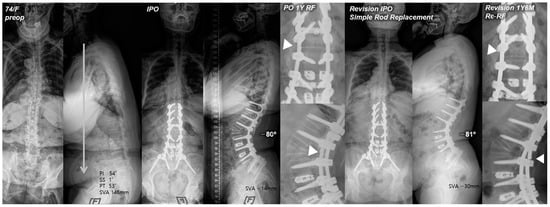

4.1. Simple Bilateral Rod Replacement

Our study findings revealed the incidence of re-RF following revision surgery due to RF to be 13%. Of the three revision methods, simple bilateral rod replacement (RR group) showed the highest incidence of re-RF. We believe that the hyper-acutely contoured posterior rods paralleling a relatively large angular correction in PSO could have progressively intensified the stress concentration and lowered the fatigue strength of each rod [17,18,19,20,21], which consequently may have led to rod-breakage. Furthermore, the fact that every re-RF in the RR group occurred consistently at the same PSO site (Figure 1) not only suggests that simple bilateral rod replacement alone has a high risk of re-RF but also proves that additional support around the PSO site is ultimately required to prevent RF and maintain sagittal balance in PSO.

Figure 1. Pre- and postoperative standing radiographs of a 74-year-old female patient. After T10-S1 posterior instrumentation with PSO on L2, PLIF on L3–5, and ALIF on L5-S1, optimal sagittal balance was achieved (SVA, −14 mm; TK, 28°; LL, −80°; PI, 54°; PT, 4°; SS, 50°). At 1 year after primary deformity correction, RF (left rod) occurred at L2. At 1 year and 6 months following revision surgery with simple bilateral rod replacement, re-RF occurred at L2–3. White triangles indicate the site of RF.